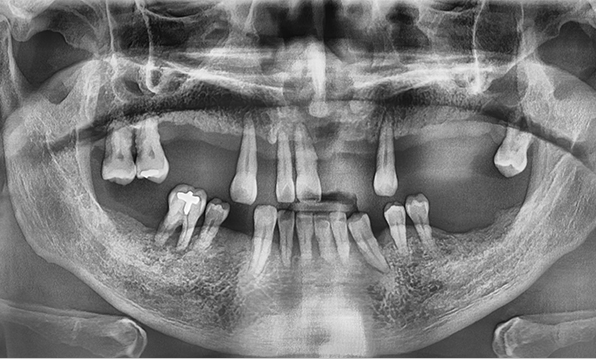

전체 임플란트는 위턱과 아래턱의 교합, 잇몸뼈의 상태 및

얼굴 변화 등 모든 것을 고려해 식립해야 합니다.

서울더자연치과는 3D 디지털 기술의 정밀 진단을 바탕으로

수술 계획을 세워 수술을 집도합니다.

잇몸뼈가 얇은 상태

잇몸뼈 충분히 이식 후 임플란트 식립

성공을 위한 노하우, 잇몸뼈 재건 기술

전체 임플란트를 해야하는 환자들은

대부분 고령의 환자들로 오랜 틀니 사용

또는 노화로 인해 치조골이

거의 남아있지 않는 경우가 많습니다.

이 때, 치조골 이식을 병행하여 잇몸뼈 재건 후 안정적인 임플란트 식립을 하고 있습니다.

치료기간 : 2021.04.12~2021.09.15